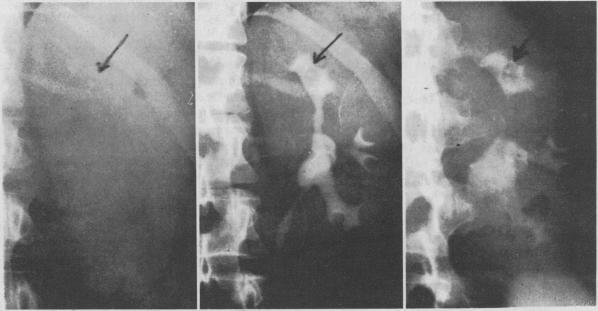

The prevalence of kidney stones has steadily risen during this century; passage of a calculus and a positive family history increase the probability of recurrence. Findings from recent studies on the cause of renal calculi have stressed crystallization and crystal aggregation of stone minerals from supersaturated urine, rather than excessive organic matrix. Absence of normal urine inhibitors of calcium salts is also stressed. Formation of calcium oxalate stones is the major problem. Therapy with decreased calcium and oxalate intake, thiazides, phosphate salts and allopurinol in various combinations has substantially decreased the prevalence of recurrent stones. The rationale for the use of allopurinol is that uric acid salts enhance the tendency for calcium oxalate to crystallize from supersaturated urine. The hypercalciuria seen in 30 percent to 40 percent of patients with oxalate stones is usually caused by intestinal hyperabsorption of calcium. Although patients with uric acid calculi constitute only a small fraction of those in whom stones form, they represent a group in whom good medical therapy, based on sound physiologic principles, has proved extremely successful. Renal tubular syndromes lead to nephrocalcinosis and lithiasis through hypercalciuria, alkaline urine and hypocitraturia, the latter an inhibitor of calcium salt precipitation. Recent advances in surgical techniques are discussed, including the rationale for removing staghorn calculi. The ileal ureter and coagulum pyelolithotomy deserve special emphasis.

本世纪以来,肾结石的患病率持续上升;结石排出及阳性家族史会增加复发概率。近期关于肾结石病因的研究结果强调,结石矿物质从过饱和尿液中结晶和晶体聚集,而非过多的有机基质。正常尿液中钙盐抑制剂的缺乏也受到关注。草酸钙结石的形成是主要问题。通过减少钙和草酸盐摄入、噻嗪类药物、磷酸盐和别嘌呤醇的各种联合治疗,已大幅降低复发性结石的患病率。使用别嘌呤醇的理论依据是,尿酸盐会增强草酸钙从过饱和尿液中结晶的倾向。30%至40%的草酸钙结石患者出现的高钙尿症通常是由肠道对钙的过度吸收引起的。尽管尿酸结石患者仅占结石形成患者的一小部分,但他们是基于合理生理原则进行良好药物治疗已被证明极为成功的群体。肾小管综合征通过高钙尿症、碱性尿液和低枸橼酸尿症导致肾钙质沉着症和结石症,后者是钙盐沉淀的抑制剂。文中讨论了手术技术的最新进展,包括去除鹿角形结石的理论依据。回肠代输尿管术和凝块肾盂切开取石术值得特别强调。